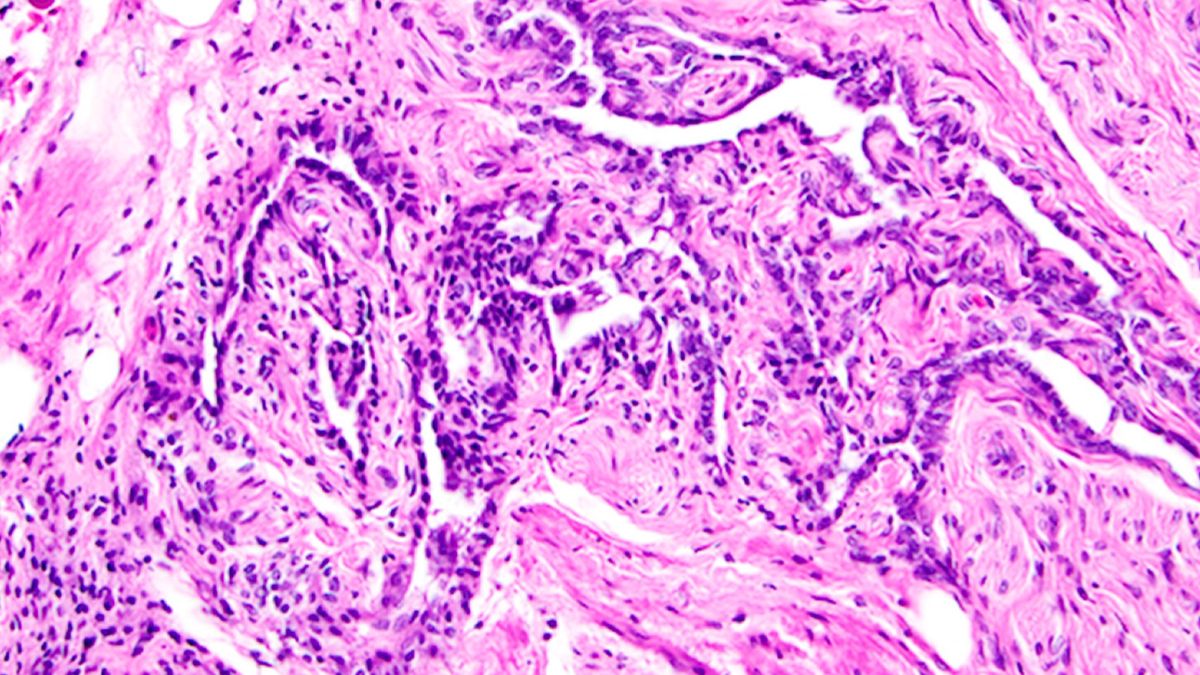

Longtemps considéré comme inutile, cet organe du corps féminin est en réalité essentiel

Le rete ovarii est une structure mal comprise du corps féminin. Reliée aux ovaires, elle pourrait être beaucoup plus essentielle à la fonction ovarienne et à la fertilité que les scientifiques ne le pensaient jusqu'à présent. The post Longtemps considéré comme inutile, cet organe du corps féminin est en réalité essentiel appeared first on Daily Geek Show.

Le rete ovarii est une structure mal comprise du corps féminin. Reliée aux ovaires, elle pourrait être beaucoup plus essentielle à la fonction ovarienne et à la fertilité que les scientifiques ne le pensaient jusqu'à présent.